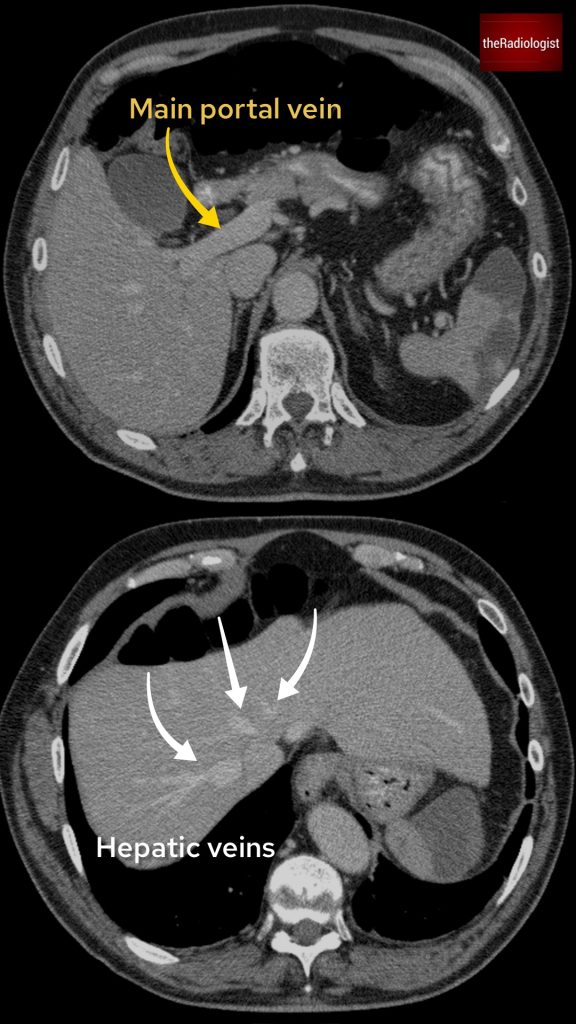

If we look at the psoas muscles on this scan below we can see there is some asymmetry . The right psoas is larger than the left and we’ve lost some of the fat planes within the muscle.

Compare the psoas muscles side by side. The right sided psoas muscle appears expanded with a loss of its normal fat planes.